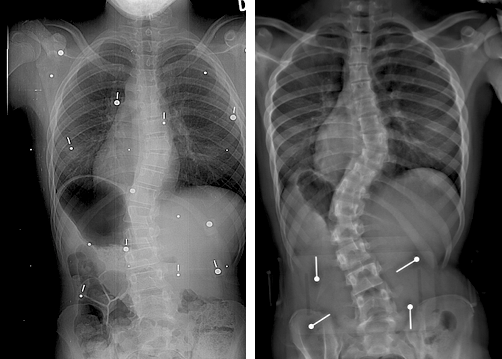

We evaluated the geometrical accuracy of the predicted models at two time-points, at t=12𝑡12t=12 and t=24𝑡24t=24 months. Because the follow-up visits were not precisely, we grouped patients with a visit between 10 and 14 months within the 1-year bin, and visits between 22 and 26 months within the 2-year bin. For the predicted models, we evaluated both the 3D root-mean-square difference of the vertebral landmarks generated and the Dice coefficients of the vertebral shapes. The results are shown in Fig. 5. We compared results using different composition for feature vectors y: 1) vertebral shape features, 2) inter-vertebral poses and 3) combination of shape+poses. Fig. 6 shows sample prediction results at 12 and 24-months for 2 different clinical groups, which are commonly seen in the scoliotic population with thoracic and lumbar deformities. The results show encouraging predicted geometrical structures which offers a globally accurate representation of how the spine deformation has progressed at different structural levels. One can observe the local shape deformation is also well captured in the predicted models.

Refer to caption

(a)

(b)

(c)

(d)

Figure 6: Examples of prediction results at 12 and 24 months based on the initial baseline 3D reconstruction. Patient cases are shown for (a) single curve left lumbar deformity, (b) major right thoracic and minor left lumbar deformity, (a) double curve right thoracic left lumbar deformity and (b) single curve right thoracic deformity.